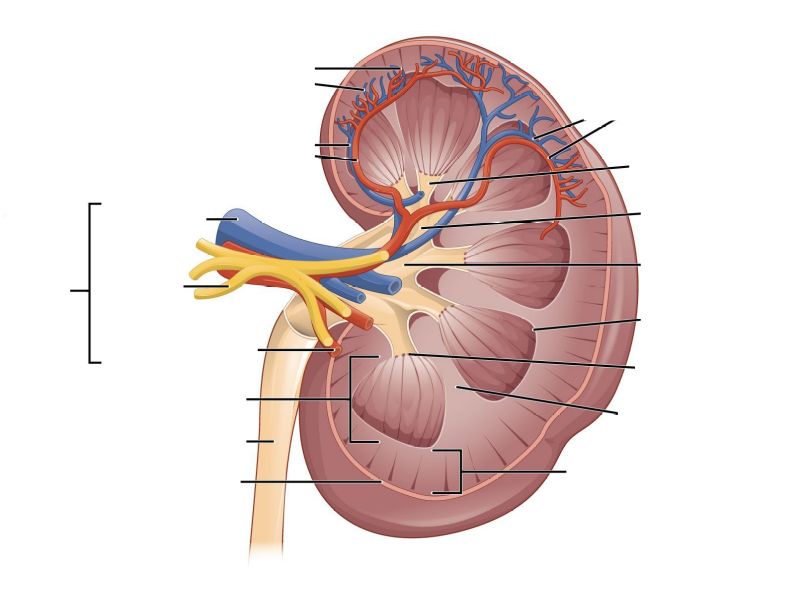

Basic anatomy of the kidney

Make an annotated drawing of the macroscopic view of the kidney.

Make an annotated diagram of a nephron, including the juxtaglomerular apparatus. Indicate the flow of blood and water in each part, and how solutes are filtered, secreted and reabsorbed.